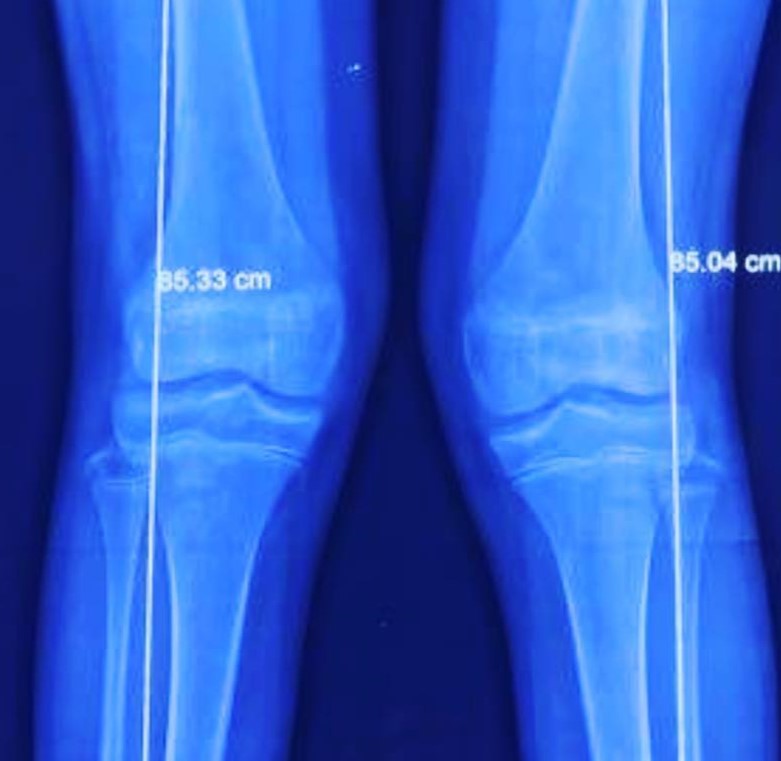

Rodillas en valgo

Rodillas en valgo con rótula alta